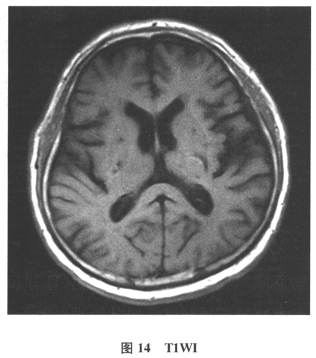

[多选题]患者男,61岁。因“发作性头晕2年,加重伴记忆力下降、走路不稳3月余”就诊。查体:BP140/70mmHg;意识清楚,构音障碍,近期记忆力及远期记忆力

[单选题]患者男,61岁。因“发作性头晕2年,加重伴记忆力下降、走路不稳3月余”就诊。查体:BP140/70mmHg;意识清楚,构音障碍,近期记忆力及远期记忆力